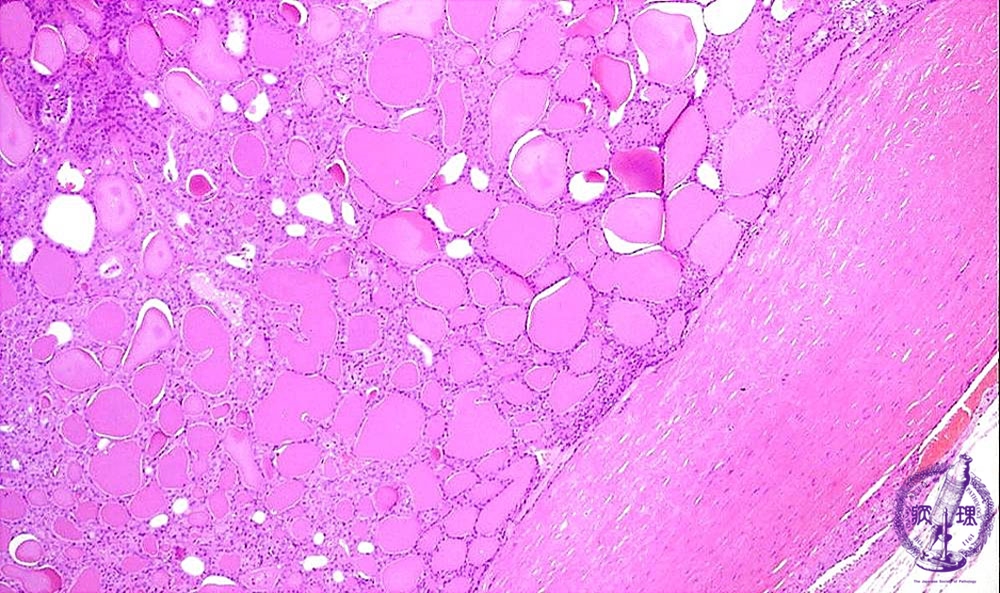

Microscopic findings (HE stain, low power view). The tumor is composed of small follicles and surrounded by thick fibrous capsule.